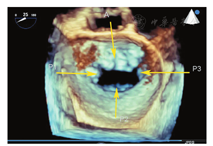

MR介入治疗术前和术中,经常使用三维TEE的X-plane双切面(包括二尖瓣交界处二腔心切面及三腔心切面)来评估二尖瓣解剖:二尖瓣交界处二腔心切面能清晰显示二尖瓣后叶P1及P3、前叶A2,而三腔心切面能清晰显示二尖瓣前叶A2、后叶P2。也可通过二尖瓣的"三维外科视野"立体显示二尖瓣前后叶(图9)。

超声心动图在MR介入术中起着不可或缺的作用,下面以目前最为成熟的经导管二尖瓣夹合术MitralClip为例,阐述MR介入术中的超声评价。MitralClip是在TEE实时监测和引导下的操作,所有的导管操作由TEE监测和引导[16]。TEE首先引导房间隔穿刺,使得房间隔穿刺点距二尖瓣瓣环平面的高度3.5~4 cm(图11)。之后,TEE引导输送系统进入左心房并调弯、顶端垂直指向二尖瓣口。接着,TEE引导夹合器在二尖瓣上方定位,夹合器进入左心室,引导夹合器捕获和夹合瓣膜。夹合器捕获瓣膜位置,应该位于彩色多普勒显示反流束最大处。在整个手术过程中,两个超声切面非常重要,为手术的工作切面(X-plane双切面),包括三腔切面(左心室长轴切面)及二尖瓣交界处两腔切面(图12),前者可以显示二尖瓣A2、P2的位置,捕获瓣膜前二尖瓣夹合器应该在这个切面显示为"V"形,此时瓣夹合器臂与二尖瓣开放线垂直,分别位于A2、P2的位置,在该切面通过调整夹合器位置可使得夹合器更靠近前叶或后叶;后者显示P1,A2,P3,捕获瓣膜前二尖瓣夹合器在该平面应该为直线形,在该切面通过调整夹合器位置可使得夹合器更靠近内交界(3)或外交界(1)。另外一个工作切面为三维超声心动图的"二尖瓣外科视野",可以整体观察夹合器的位置、臂指向的方向(图13)。目前有限经验显示,经心尖二尖瓣夹合术(ValveClamp)术中超声指导和MitralClip总体上类似,但仍有部分差异,其超声规范尚在探索中。